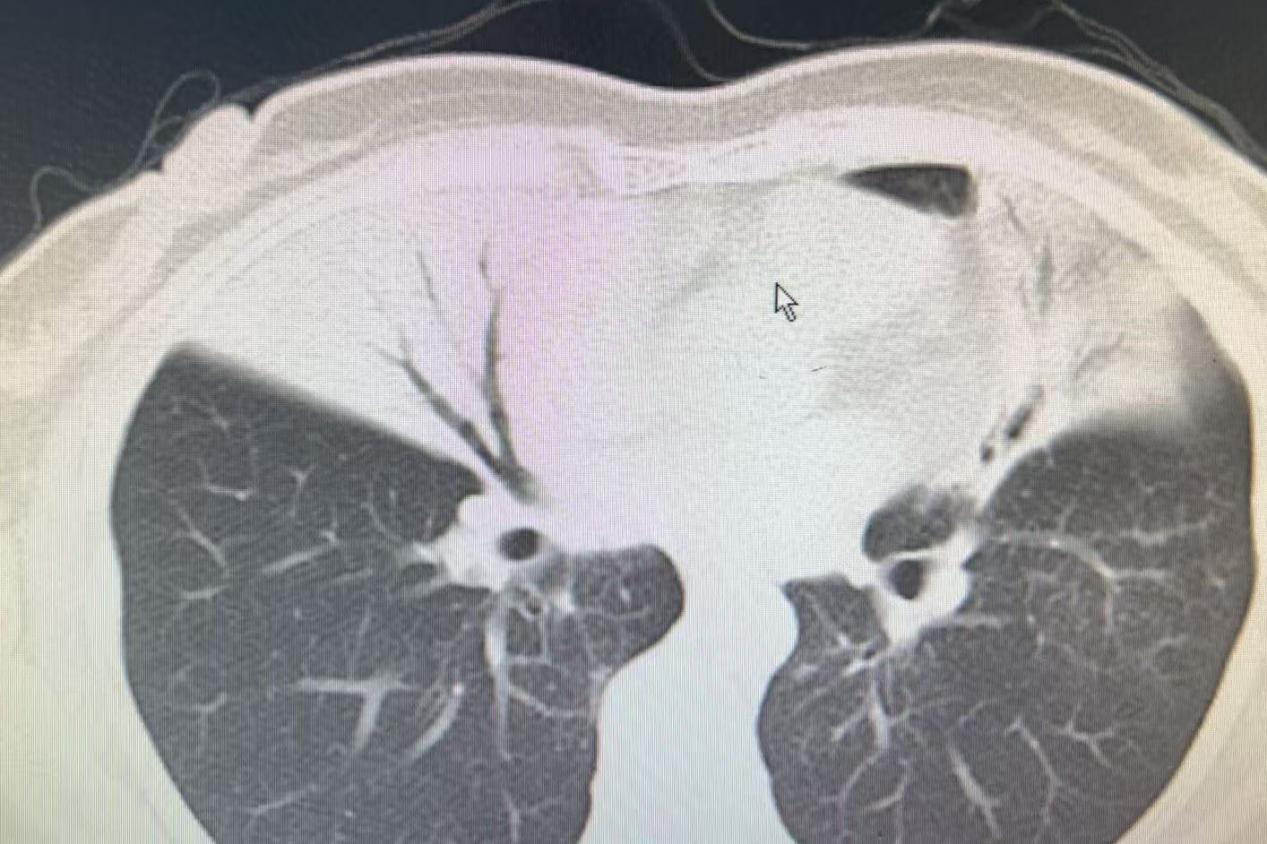

患者,女性,52岁,因“右侧胸痛1月”入院。1个月前,患者出现右侧胸痛,当地医院CT检查显示右肺中叶及左肺上叶大片实变影,初步诊断为肺部感染,给予哌拉西林舒巴坦抗感染治疗,但效果不佳。随后,患者接受了气管镜检查,灌洗液送检二代高通量测序(NGS),结果显示为金黄色葡萄球菌感染,遂调整为左氧氟沙星抗感染治疗。2周后复查胸部CT显示病变仍无明显好转。随后,患者经介绍前往清华大学附属垂杨柳医院就诊。

▲患者胸部CT影像,显示右肺中叶及左肺上叶大片实变影